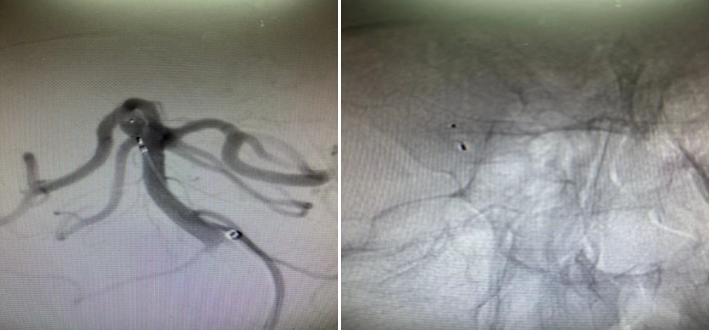

患者28岁,因反复头痛头晕在当地医院检查提示基底动脉顶端动脉瘤。患者患有高血压,基底动脉动脉瘤随时可能破裂致自发颅内出血,严重时可能致残致死。因该位置手术风险较大,地州医院无法手术,于是患者辗转来到昆医大附二院神经外科一病区。入院后,神经外科一病区为患者行全脑血管造影,提示右侧小脑上动脉动脉瘤。

该动脉瘤位于右侧小脑上动脉及大脑后动脉之间,宽颈,常规栓塞较为困难,支架置入难度较大,若置入支架辅助栓塞,后期患者需抗凝抗血小板治疗较长时间;开颅手术夹闭则创伤较大,恢复时间较长。蒲军主任在仔细阅读患者DSA造影资料后,提出可行现最新的自膨式瘤内栓塞系统治疗该动脉瘤,在告知家属病情及相关情况后,患者家属同意行该手术。

经过周密的术前检查,在蒲军主任的指导下,黄晓斌及张明副主任医师、王和平博士团队顺利为患者实施了自膨式栓塞系统小脑上动脉动脉瘤栓塞手术。手术时间20分钟,完整填塞动脉瘤,术后造影提示动脉瘤未显影,周围各支重要血管血流正常。术后,患者恢复良好,无任何神经功能障碍,无需服用任何特殊药物,并于3天后出院。